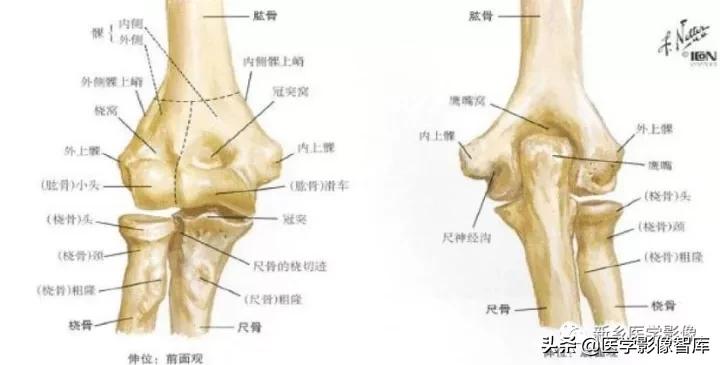

肘关节的X线解剖肘关节常规X线片包括伸肘前后位及屈肘90°的侧位(图1)。正位像肱桡关节间隙清晰,呈下凹的浅弧形;肱尺关节间隙有尺骨滑车切迹重叠而变暗,呈上凹的弧形,故而正位片上肘关节间隙呈波浪状。屈肘侧位片,肱尺关节间隙清晰,呈半环形,前为冠突,后为鹰嘴。肱桡关节掌侧清晰,背侧部分和尺骨冠突相重叠。此时通过桡骨纵轴线的延长线也穿过肱骨小头中心。

伸肘正位片上,肱骨、尺骨长轴线形成向外165°~170°的夹角,此为生理性前臂外翻角,男性一般大于女性。若小于l65°叫肘外翻,大于190°叫肘内翻,如果是180°则叫直肘(图1-1),均属异常表现。肱骨长轴与尺骨长轴在内下方的夹角谓之提携角,正常范围5°~20°之间,女大于男。